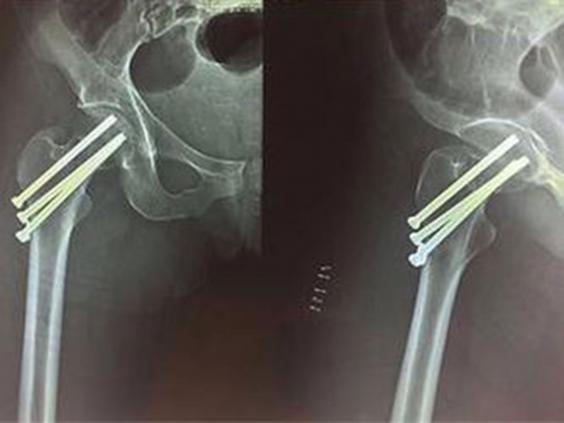

She was moved to Martinique Island for surgery, where three screws were inserted to reattach the femoral head during a four-hour long operation.